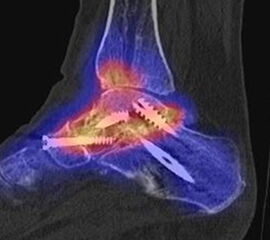

Ein weiteres Beispiel für eine im Verlauf entstandene symptomatische Arthrose in den Nachbargelenken zeigen die Abbildungen 5.3.a und b. Bei dem Patienten bestand ein Z. n. subtalarer und talo-navikularer Arthrodese vor 11 Monaten mit Beschwerden beim Abrollen im linken Sprunggelenk mit dem Gefühl „einer Sperre“. Abbildung 5.3.b zeigt die Entwicklung einer anterior betonten hypermetabolen OSG-Arthrose mit Zeichen einer teilweise knöchernen Durchbauung der subtalaren Arthrodese links. Noch keine signifikante Durchbauung der talo-navikularen Arthrodese links. Die Abbildungen 5.4.a bis c zeigen als Erklärung für Schmerzen eine symptomatische Osteochondrale Läsion in der Talusrolle bei knöcherner und reizloser Durchbauung der Arthrodesen 14 Monate nach USG- und TN-Arthrodese.

SPECT/CT zur Beurteilung von Arthrodesen

Arthrodesen gehören seit langem zu den Standardverfahren bei Fehlstellungen oder schmerzhaften Arthrosen 4546 (Graves, 2000). Eine zumindest teilweise knöcherne Durchbauung von Arthrodesen sollte in der Regel innerhalb von 6 Monaten nach der OP nachweisbar sein 647. Eine unvollständige oder fehlende Fusion nach Arthrodese kann permanente Schmerzen verursachen, was sich mit der SPECT/CT nachweisen lässt. Abbildung 5.1. zeigt den Fall eines Patienten mit persistierenden Beschwerden 1 Jahr nach calcaneo-cuboidaler Arthrodese, es besteht ein erhöhter Knochenmetabolismus im Bereich der Arthrodese bei teilweise noch abgrenzbarem Gelenkspalt; kein Nachweis von Anschlussarthrosen in den benachbarten Gelenken. Persistierende Beschwerden nach Arthrodese können jedoch auch durch Überlastungen angrenzender Gelenke entstehen, die dann in Arthrosen münden 48. Ein entsprechendes Beispiel ist in Abbildung 5.2. dargestellt, die den Verlauf bei einer Patientin mit Z. n. Arthrodese wegen einer talonavicularen Arthrose zeigen.